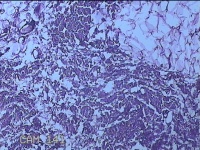

外阴部包块

性别

女

年龄

37岁

临床诊断

皮脂腺囊肿

一般病史

外阴部起包块一月余。

标本名称

大体所见

灰白暗红色包块2.3x1.8x0.8cm一个,表面糜烂,切开包块呈实性,切面灰白淡黄色,质软。

有那么点像脂肪瘤。